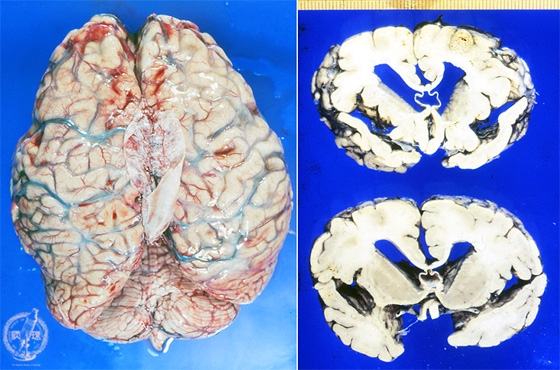

Macroscopic findings: Brain demonstrated atrophy mainly in the frontal lobe. Cerebral sulci widened with the gyri prominent. The cut surface (right) also revealed the widening of sylvian fissure, indicating massive cortical atrophy.